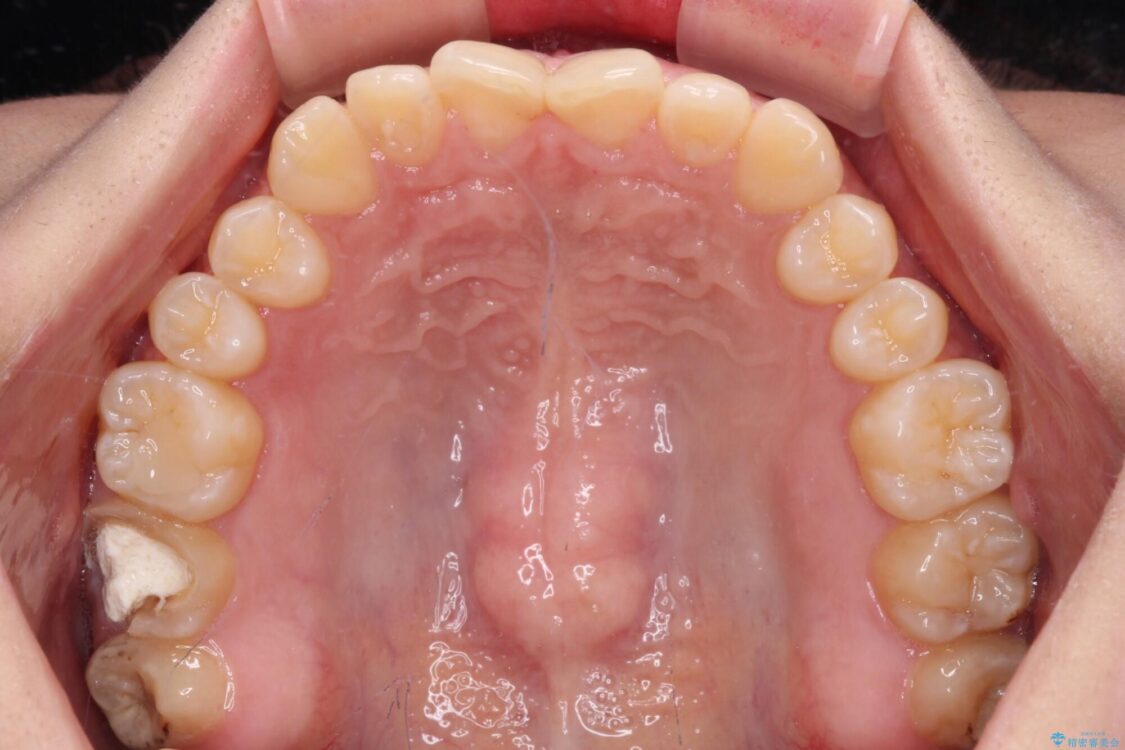

治療前

• 治療途中の奥歯と矯正治療の後戻り インビザライン・ライトによる矯正治療 治療前画像